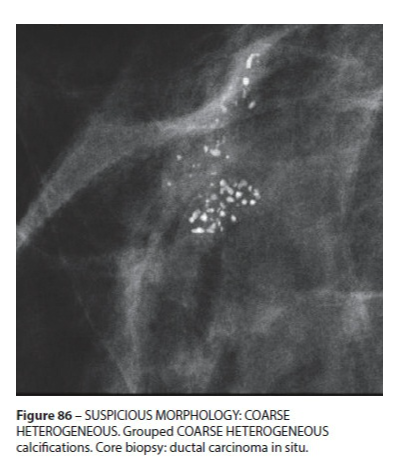

Calcifications Grossières Hétérogènes

- Irrégulières, Coalescentes

- Plus Petites que les Dystrohpiques